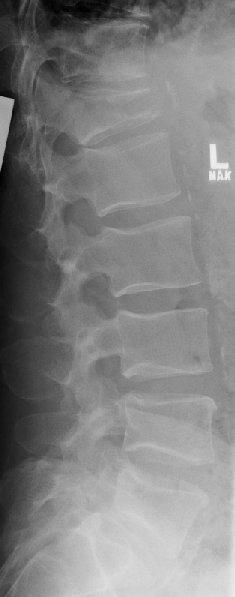

Return to Compression Fracture (Lumbar)